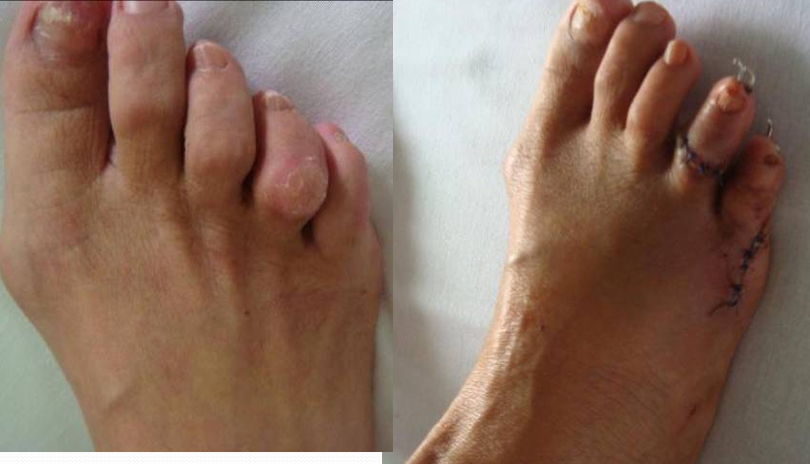

例2:芦XX,男,21Y。

例3:朱XX,男,23Y。

例4:罗XX,女,60Y。

左足:第2-5趾爪形趾。

右足:第4趾爪形趾,趾间关节胼胝,疼痛。

术式:左足:第1跖趾关节融合+第2-5跖趾关节成形术;右足:第4趾间关节融合+第5跖趾关节成形术